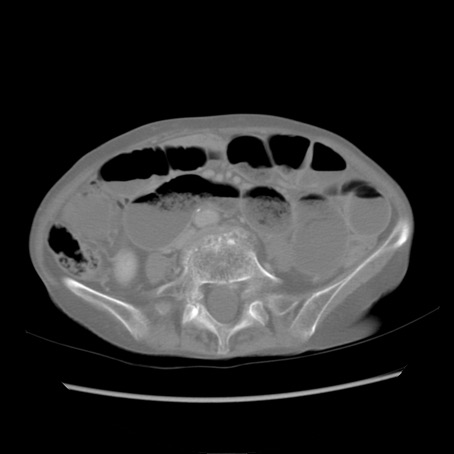

症例25(横断像)

【症例】80歳代女性

【主訴】胸のつかえ感

【現病歴】約9時間前に食後から胸のつかえた感じあり、嘔吐あり、来院。

【既往歴】胃癌(全摘)、胆摘、虫垂炎

【身体所見】心窩部に圧痛あり、反跳痛なし。

【データ】WBC 5700、CRP 0.05